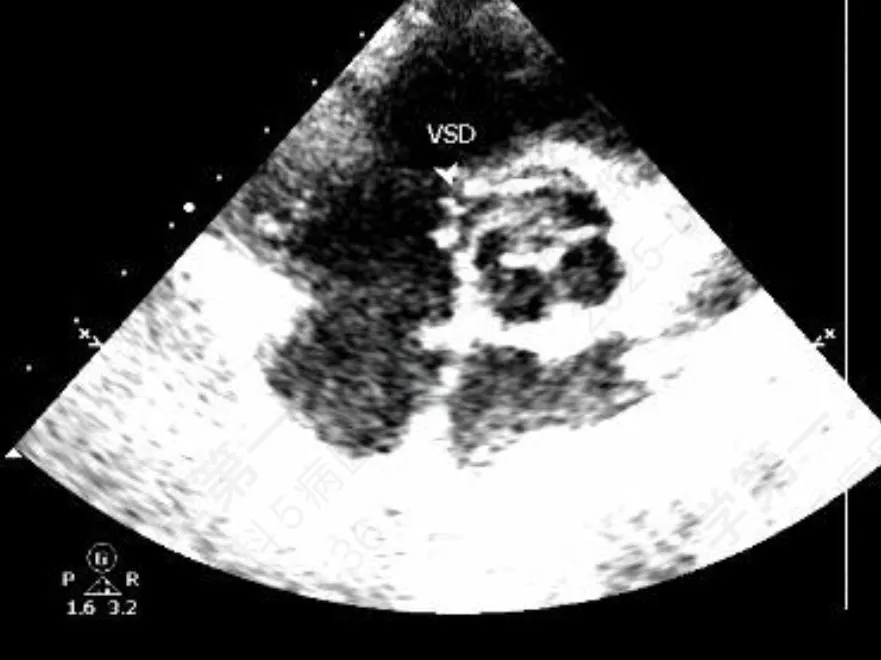

门诊心脏彩超提示:

超声多切面示:室间隔膜周部可见连续中断,局部不规则向右室膨出,呈“囊袋状”,断端回声增强,测缺口大小:左室面6.5mm、右室面2.5mm,隔瓣下残缘5mm,彩色血流示:室水平左向右分流,Vmax 473cm/s,Pgmax 89 mmHg。

术前超声与DSA复测

VSD(膜周部):室间隔膜部瘤,左室面6.5mm,右室面呈“瘤样”结构,瘤体深度7mm,出口2mm。

该病灶呈现为“长隧道、大瘤底、小出口”的细腰形态,且位置紧邻主动脉瓣与三尖瓣,解剖结构较为复杂。此形态特征使得可降解封堵器在植入过程中的定位与释放面临较大挑战。